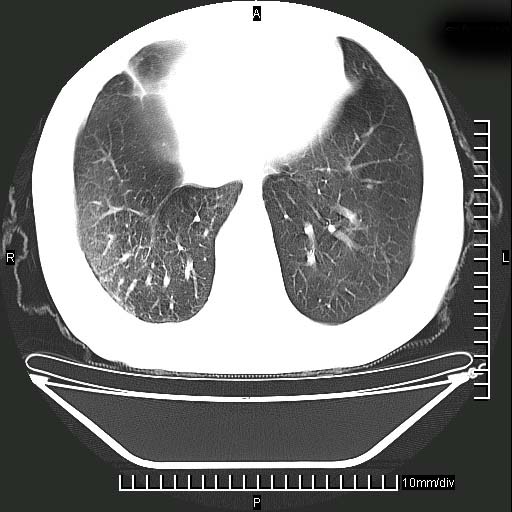

既往肺结核,近10几天,咳嗽,咳痰,右侧胸痛,疼痛较明显,右上肺斑块考虑结核灶胸膜粘连,增强,可惜动脉期没有定好,未见强化,可延迟4分后又见较明显强化,中心见低密度影,如果说结核是边缘强化,可这个灶强化的面积挺大的,让人很挠头。

动脉期